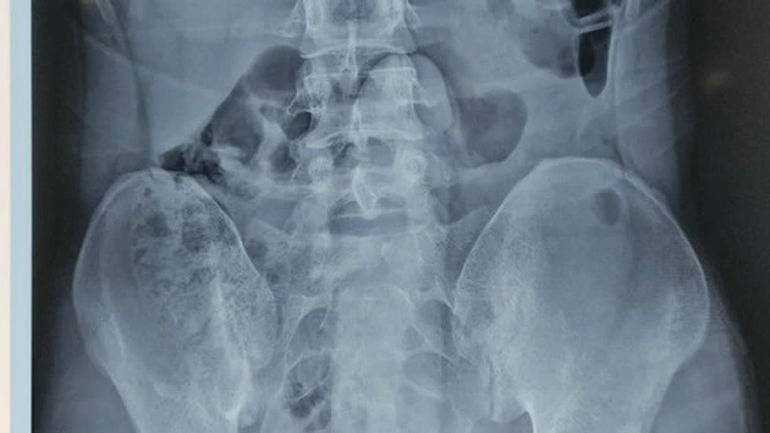

Hình ảnh của dị vật được chụp bằng phim Xquang. (Ảnh: được cung cấp bởi Bệnh viện)

Tại bệnh viện, sau khi thăm khám và chụp Xquang, các bác sĩ đã phát hiện một dị vật có hình dạng giống dương vật ở sâu trong trực tràng. Do đó, bệnh nhân đã được chuyển lên Khoa Phẫu thuật - gây mê hồi sức để loại bỏ dị vật.

Đây là một chiếc dương vật giả, có kích thước là 25x5 cm.